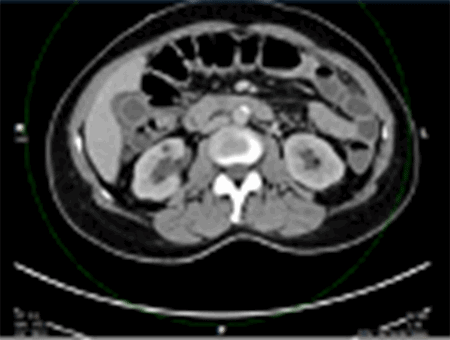

One week after her first cycle of chemotherapy, she presented to our emergency department with complaints of right upper quadrant abdominal pain. She described the pain as a sharp, stabbing in nature that was acute in onset associated with nausea and vomiting. She denies any previous episodes of similar pain. On physical exam, she was afebrile, vital signs were stable, and tenderness in the right upper quadrant was noted. Her white blood cell count was 10,000, and liver function tests revealed an elevated AST, ALT, and alkaline phosphatase. An abdominal CT scan showed marked gallbladder wall thickening without obvious cholelithiasis (Figure 1), while a HIDA scan was negative for cholecystitis with no obstruction of the cystic or common bile duct (Figure 2).

Figure 1. CT Scan Revealing Markedly Thickened Gallbladder Wall with Surrounding Pericholecystic Fluid. Published with Permission